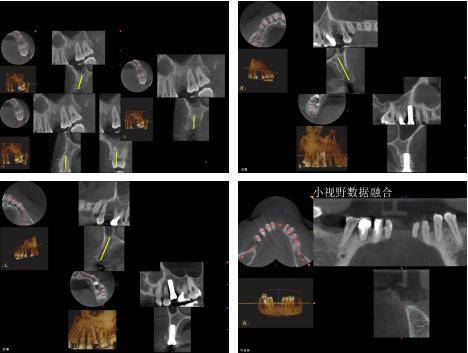

У области оралне имплантације, ЦБЦТ је постигао добре резултате у дизајнирању хируршких планова, симулацији имплантата и изради хируршких водича.

Подаци добијени ЦБЦТ-ом се увозе у софтвер за виртуелно пројектовање имплантата треће стране, који може да увезе ЦТ податке вилица за 3Д реконструкцију и реконструише комплетну анатомију вилице сваког пацијента. Клиничар може користити софтвер да јасно прикаже специфичну морфологију анатомије вилице у сагиталној, короналној и попречној равни, посматра положај симулиране локације имплантата у односу на суседне важне анатомске структуре, избегава важне анатомске структуре, смањује ризик од операције и дизајнирати симулирани хируршки план.